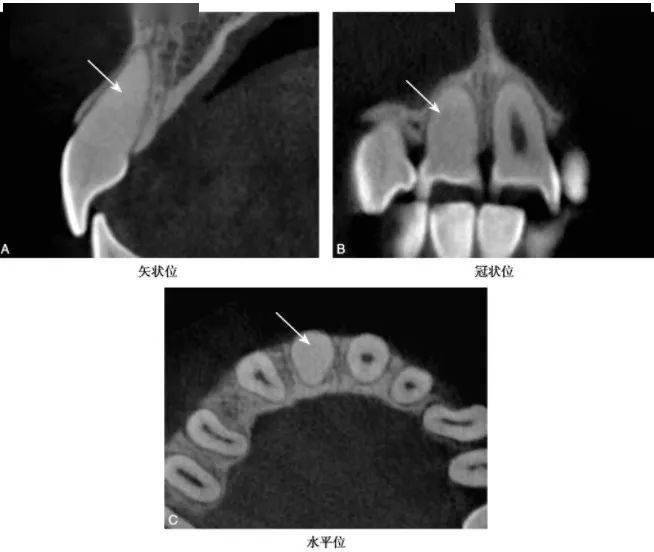

(3)弥散性钙化表现为正常的髓室及根管轮廓的消失(图5)bccbch币。

图2-2-5 A1弥散性钙化

CBCT示A1髓室、根管正常影像消失bccbch币,呈均匀近牙本质密度影(白色箭头)

(4)有些较大的髓石可能影响根管口的探查,如术前不熟悉根管系统的解剖特点,可能造成医源性意外(图6)bccbch币。

图2-2-6 B1弥漫性钙化伴侧穿

CBCT矢状位示B1弥散性钙化bccbch币,自舌侧窝至唇侧牙颈部见侧穿(白色箭头)